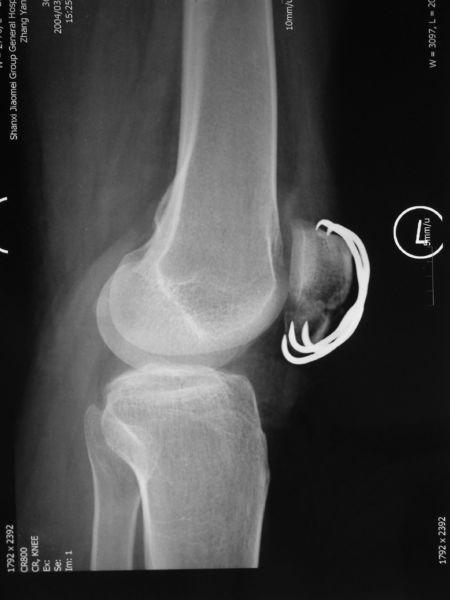

首先,让我们来了解一下这个让人头疼的髌骨骨折。髌骨,也就是我们常说的膝盖骨,位于膝盖前方,是人体最大的籽骨。它不仅起到保护膝关节的作用,还能帮助我们在运动时更好地发力。由于各种原因,髌骨骨折却成了不少运动爱好者的噩梦。